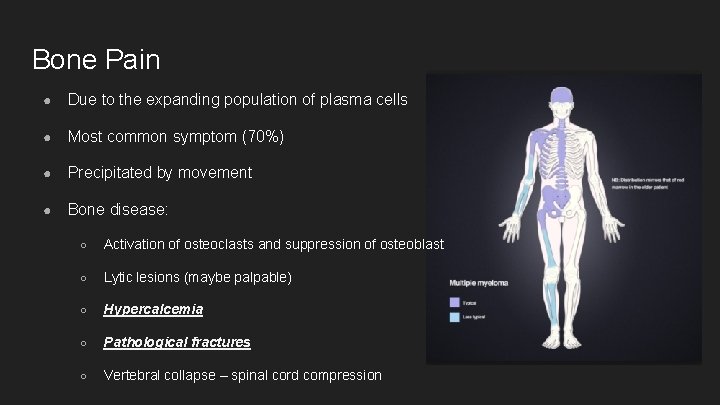

Bone Pain ● Due to the expanding population of plasma cells ● Most common symptom (70%) ● Precipitated by movement ● Bone disease: ○ Activation of osteoclasts and suppression of osteoblast ○ Lytic lesions (maybe palpable) ○ Hypercalcemia ○ Pathological fractures ○ Vertebral collapse – spinal cord compression